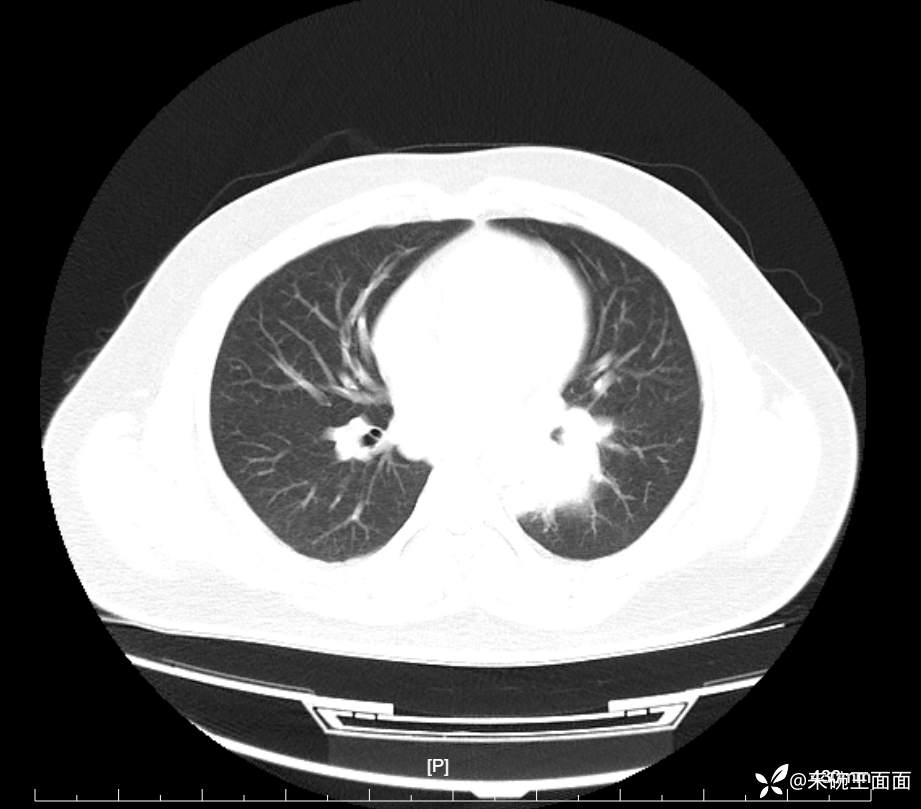

性别:男

年龄:27岁

主诉:胸闷胸痛数月余,休息后可自行缓解,无咯血症状。

个人史:数年吸烟史,具体不详。